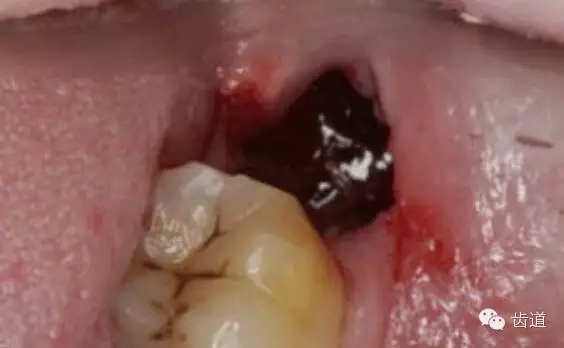

3)臨床表現(xiàn)及診斷

診斷標(biāo)準(zhǔn):拔牙2~3天后仍有劇烈疼痛,并可向耳顳部、下頜下區(qū)或頭頂部放射,一般陣痛藥物不能止痛;拔牙窩內(nèi)空虛,或有腐敗壞死的殘留血凝快,如用棉球蘸取內(nèi)容物嗅之,有惡臭。